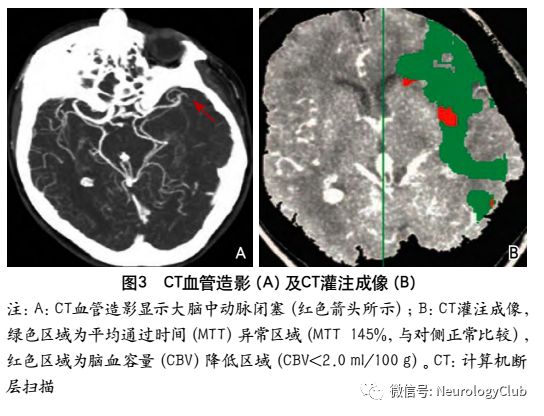

CT灌注成像是用来识别AIS后缺血半暗带的另一种成像技术,通过对各循环参数的判定来识别缺血半暗带。CTP常见的参数有:CBF、CBV、相对脑血容量(relative cerebral blood volume,rCBV)、MTT、达峰时间(time to peak,TTP)、相对平均通过时间(relative mean transit time,rMTT)、相对延迟时间(relative delay time,rDT)。随着CT对团注造影剂的扫描形成信号清除曲线,继而生成半定量CBV和CBV图。当缺血更为严重时,则CBV萎陷。

CT灌注成像对于梗死核心灶标记为CBV降低的区域,CBF与MTT以低于界定的阈值(CBV<2ml/100g、CBF<20ml/100g/min及MTT>8s)来显示脑的异常灌注区缺血半暗带为脑梗死核心区与异常灌注区域之间的差异区域(图3)